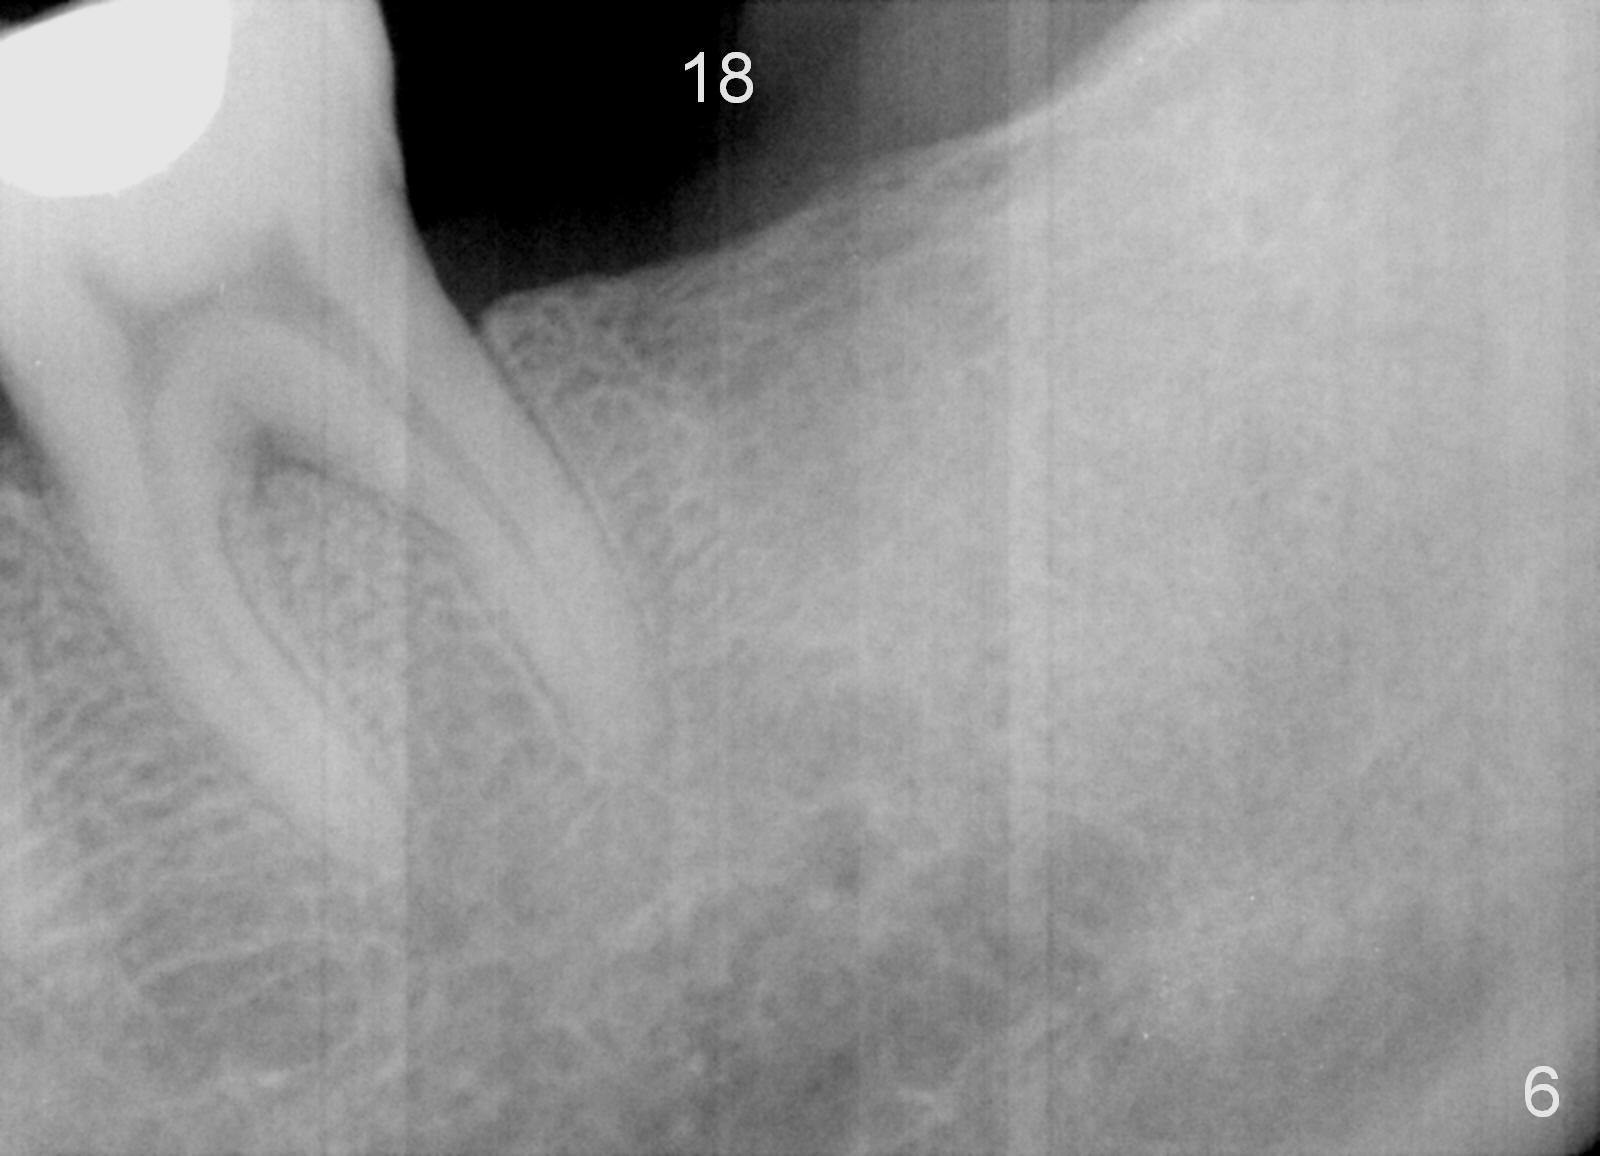

A 51-year-old man has lost #18 for more than 10 years (Fig.1,6). There appears to be sufficient bone height for implant (15 mm (Fig.7 (red dashed line: the superior border of the Inferior Alveolar Canal))). Prepare 4 mm implant spacer and SM starter drill and 2 mm pilot drill at 12 mm. Take PA. Palpation reveals that the edentulous ridge is wide. Place an implant in the middle of the ridge (buccolingually).